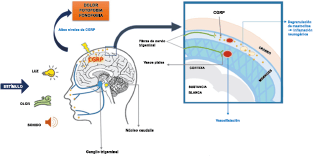

Los terminales axónicos de las fibras nerviosas nociceptivas que inervan la duramadre contienen neuropéptidos vasoactivos CGRP, sustancia P, neurocinina A y péptido activador de la adenilato ciclasa pituitaria (PACAP)(25) (Figuras 13 y 14), que se cree que son liberados tras la estimulación que causa la vasodilatación de los vasos durales y piales(26) (Figura 15).

El CGRP está ampliamente distribuido, incluso en el cuerpo estriado, la amígdala, el hipotálamo, el tálamo, el tronco encefálico y el TCC(69). Dentro de las vías trigeminovasculares aferentes primarias, la expresión de CGRP es más alta en el ganglio del trigémino sensorial y sus proyecciones de fibras Aδ y C a los vasos sanguíneos cerebrales y durales, así como centralmente a la médula espinal(70), donde puede afectar proyecciones ascendentes de segundo orden. Se han identificado receptores de CGRP funcionales y sitios de unión en las células del músculo liso de la arteria dural y en los ganglios del trigémino, el tálamo, el hipotálamo, la amígdala, la corteza y el tronco encefálico(71).

El CGRP es un potente vasodilatador que, cuando se administra a personas que padecen migrañas, se sabe que desencadena ataques(72). Se libera durante los ataques espontáneos(73) o provocados(74), que pueden inhibirse mediante el tratamiento con triptanos(75). Además de sus efectos vasculares, CGRP se ha convertido en un modulador clave de la función neuronal, que tiene efectos importantes en los sistemas de neurotransmisores como el sistema glutamatérgico(76). Sobre la base de los datos clínicos(77), se inició un esfuerzo para desarrollar antagonistas de los receptores de CGRP: los “gepantes”: telgacepant demostró una eficacia mejor que el placebo y comparable a los triptanos(78), como el primer antagonista oral del receptor de CGRP con excelente tolerabilidad a largo plazo(79) y también fue bien tolerado en pacientes que estaban siendo investigados por enfermedad arterial coronaria(80). Sin embargo, el desarrollo de telgacepant se detuvo cuando surgieron problemas con las enzimas hepáticas en un estudio preventivo, que resultó bastante positivo(81). Este efecto no se ha informado con rimagepant(82) Los ditanes, tienen como mecanismo el ser agonistas selectivos del receptor 5-hidroxitriptamina tipo 1F (5-HT1F) en la vía trigeminal, hasta ahora ha demostrado no tener efecto vasoconstrictor asociado. Lasmiditán ha sido hasta la fecha de elaboración de esta revisión la primera molécula aprobada por FDA. (Figura 35)